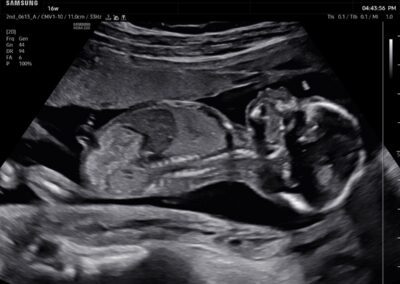

Comprehensive, advanced and expert MFM care for high-risk pregnancies

- Fetal anomalies